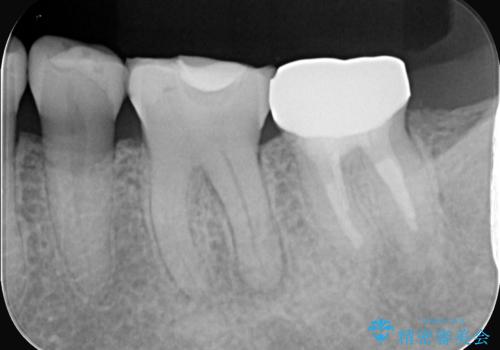

- 2日前から歯の痛みが続くという主訴でご来院されました。診察の結果、**不可逆性歯髄炎(歯の神経の重度の炎症)**と診断。レントゲンでは、歯髄腔が狭くなり、根管が石灰化している難症例であることが確認されました。患者様の大切な歯を残すため、歯科用顕微鏡を用いた精密根管治療を行うことで、狭く、見えにくい根管を正確に探し出し、治療を完了させる計画を立案しました。

今回の治療は、特に難易度の高い石灰化した根管が対象でした。まず、治療中の細菌感染を防ぐためにラバーダムを使用。次に、歯科用顕微鏡で治療部位を何十倍にも拡大しながら、狭窄した根管の入り口を探し、慎重に拡大・清掃を行いました。顕微鏡を用いることで、肉眼では不可能だった根管内部の細かい構造を確認しながら、感染源を徹底的に除去することができました。これにより、難症例の奥歯でも再発リスクを抑えた適切な処置を行うことができ、治療後に痛みは解消。大切な歯を長期間にわたり保存することができました。